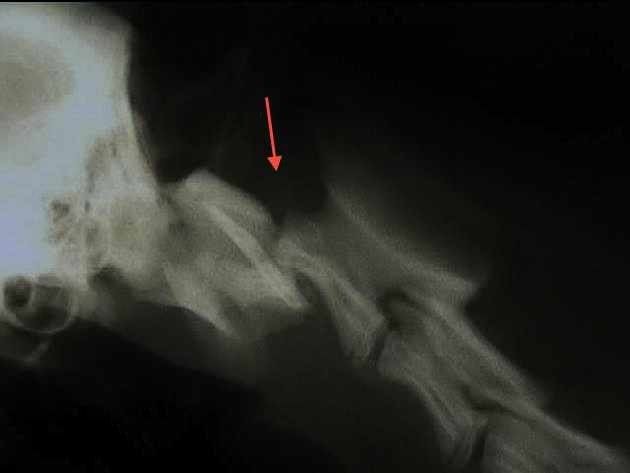

X-ray of limbs:

For the search for fractures but also the evaluation of various joint problems such as osteoarthritis or dysplasia.